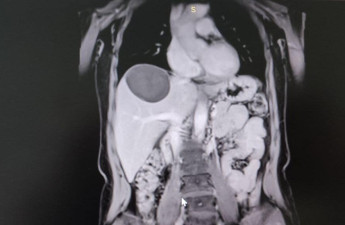

Врятували маму й немовля: на Волині оперували жінку з величезною кістою

Кіста почала активно рости на останніх термінах вагітності: консиліумом лікарів вирішено, що доцільно буде прооперувати жінку вже після пологів. Пологи відбулися природнім шляхом.